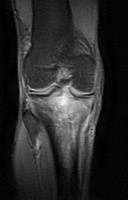

MRI

3.jpg

PD脂肪抑制序列

股骨外侧髁前外侧面、胫骨近端及髌骨上极可见异常信号(T1加权像低信号,T2/PD脂肪抑制序列呈不均匀高信号)浸润性病变,伴有边界不清的过渡带。可见少量骨外成分。